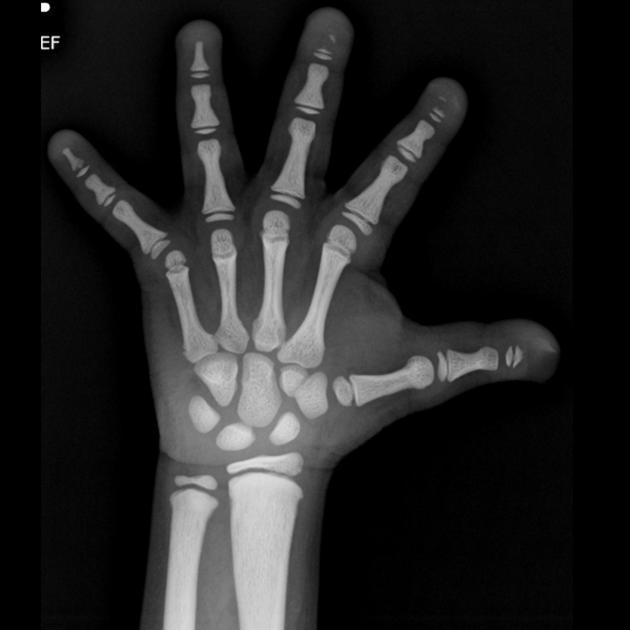

Type I acrocephalosyndactyly

CNS anomalies, congenital cardiac anomalies (10%), congenital genitourinary anomalies, symphalangism.

Triad:

1. craniosynostosis: brachycephaly

2. syndactyly

3. maxillary hypoplasia

Other: tower-shaped head and prominent forehead, hypertelorism, intellectual retardation (IQ however can be normal), exophthalmos, dehiscent jugular bulb, enlarged emissary veins of the skull

Defect on the fibroblast growth factor receptor 2 (FGFR2)